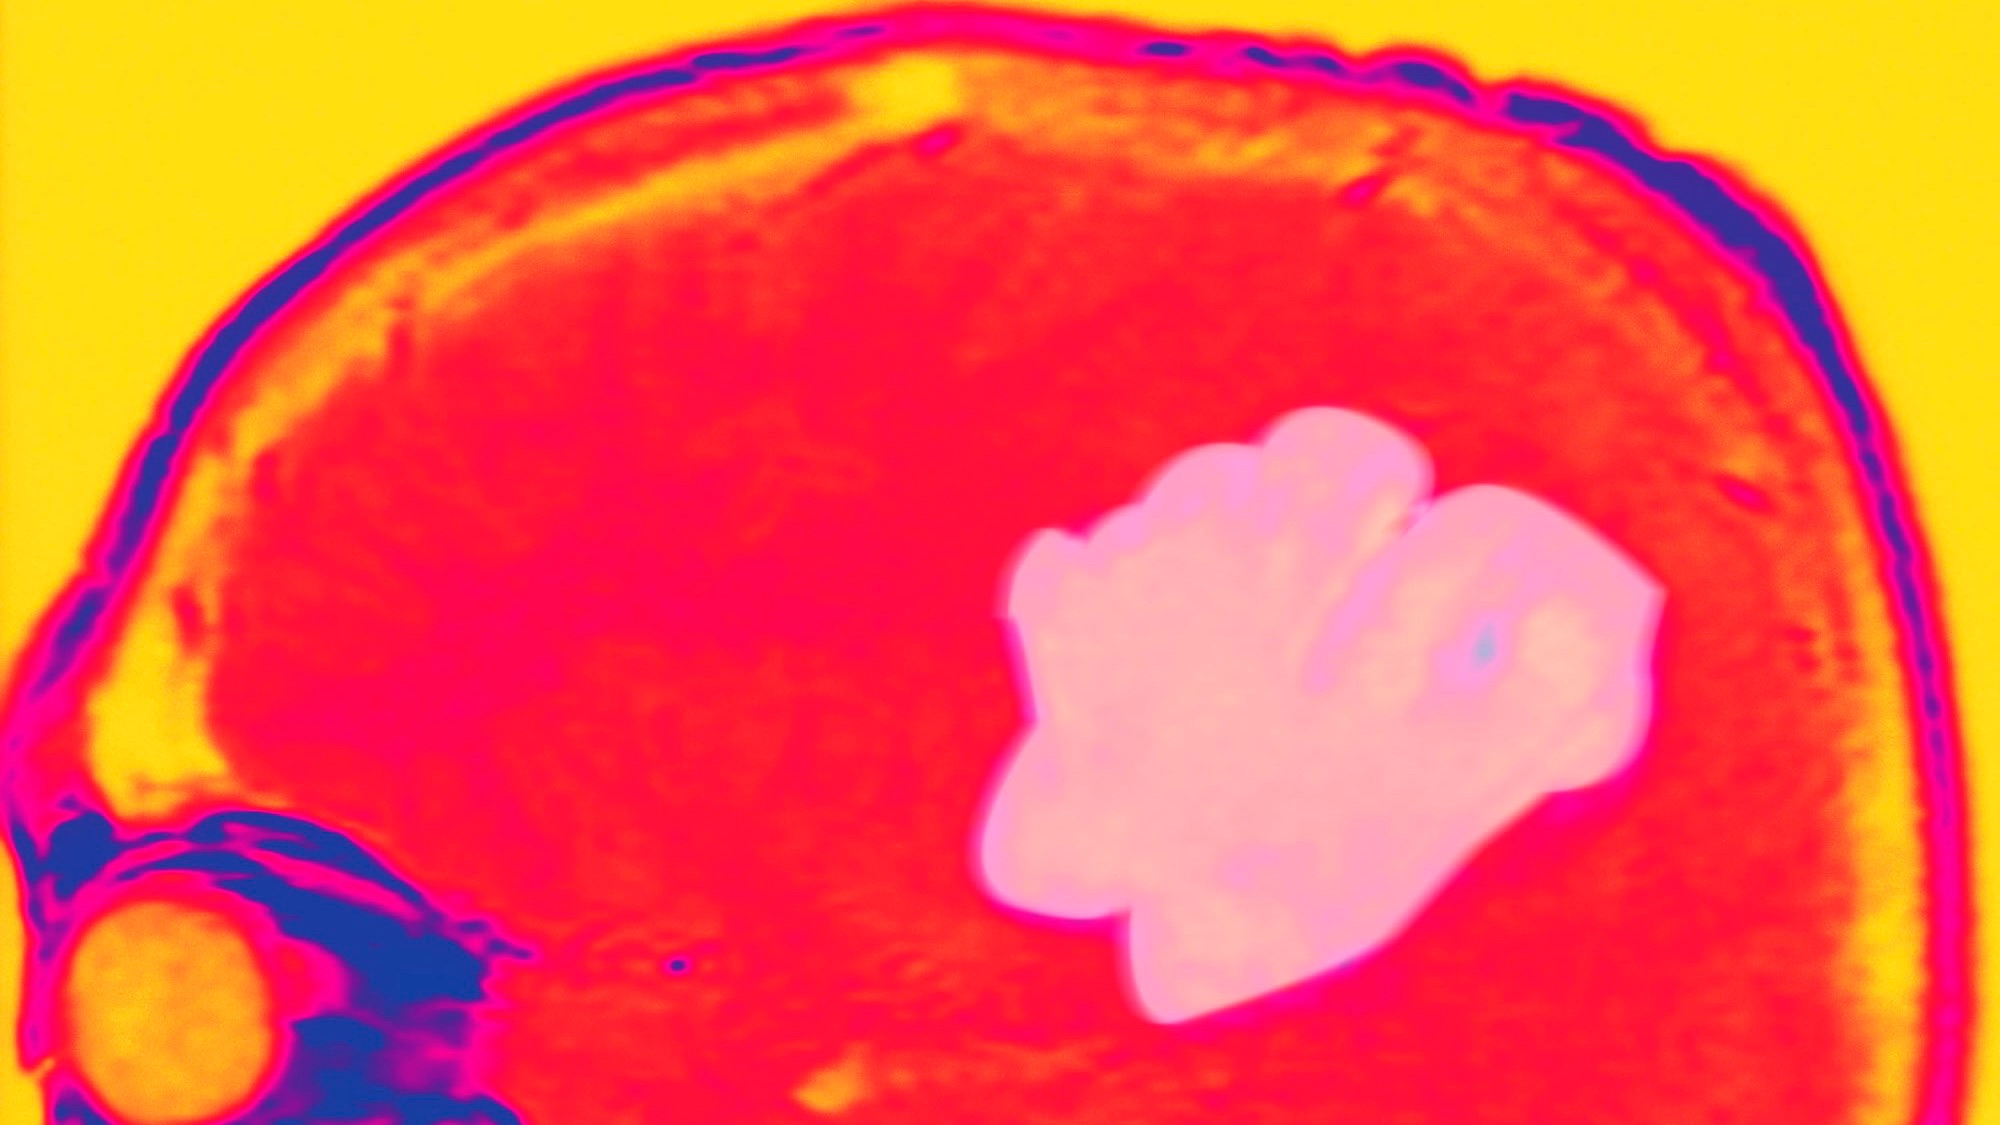

Glioblastoma. Absence Of Edema, Generalized Epileptic Seizures Due To Disseminated Cells Which Have Invaded The Cortical Region. Gadolinium Enhanced Mri T1. (Photo By BSIP/UIG Via Getty Images)

Glioblastoma, a type of brain cancer, imaged for a study investigating why some patients with this cancer live remarkably longer than others. Image: BSIP/UIG Via Getty Images

The project aims to understand the genetic makeup of survivors of fast-moving cancers, with a focus on three aggressive forms — pancreatic cancer, metastatic small cell lung cancer, and a rare brain cancer called glioblastoma IDH wild type. The study focuses on those in part because of its founder’s personal experience. Nicolas Wolikow, the CEO and co-founder of Cure51, the biotechnology company underwriting the study, lost his mother to small cell lung cancer three years ago and his father currently has blood cancer, he told Undark.